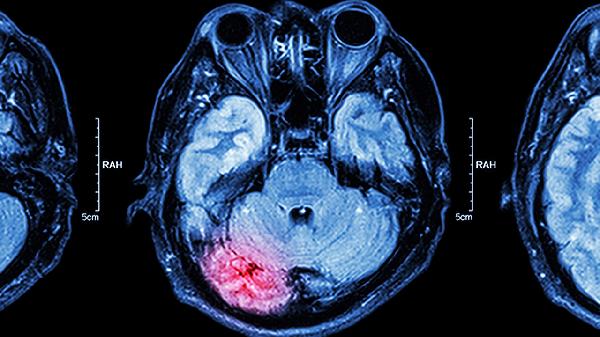

脑肿瘤患者可以适量吃富含优质蛋白的食物如鸡蛋、鱼肉,也可遵医嘱使用替莫唑胺胶囊、甘露醇注射液等药物。建议及时就医,在医生指导下结合病情调整饮食和用药方案。

适用于脑肿瘤引起的颅内高压,通过渗透性脱水降低颅压。输注过程中需监测电解质平衡,肾功能不全者需调整剂量。可能出现一过性头痛等反应。